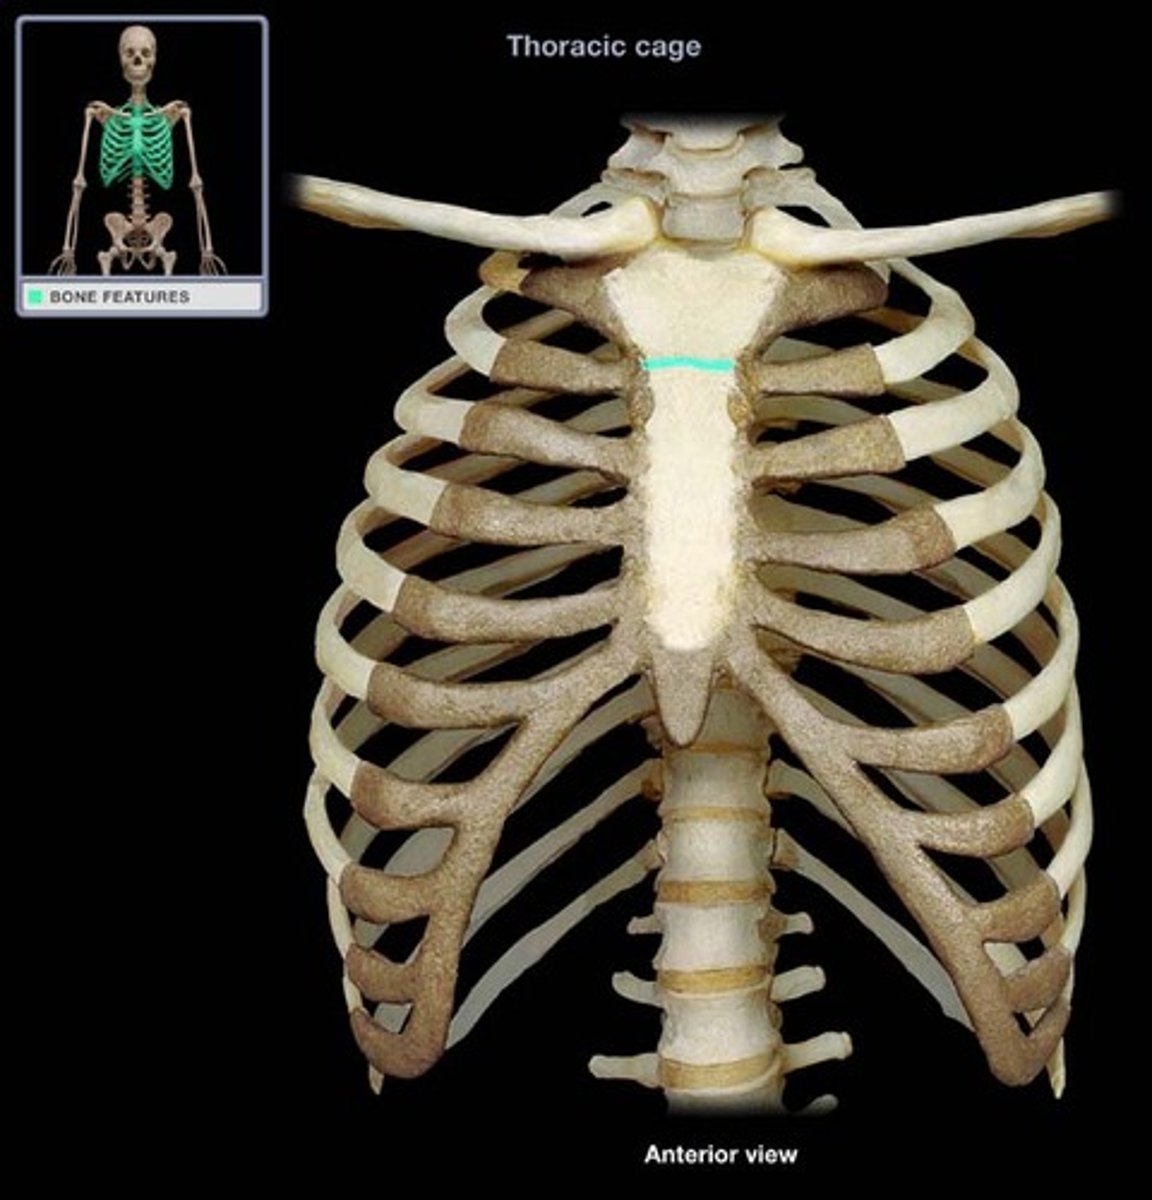

sternal angle

What is this structure?